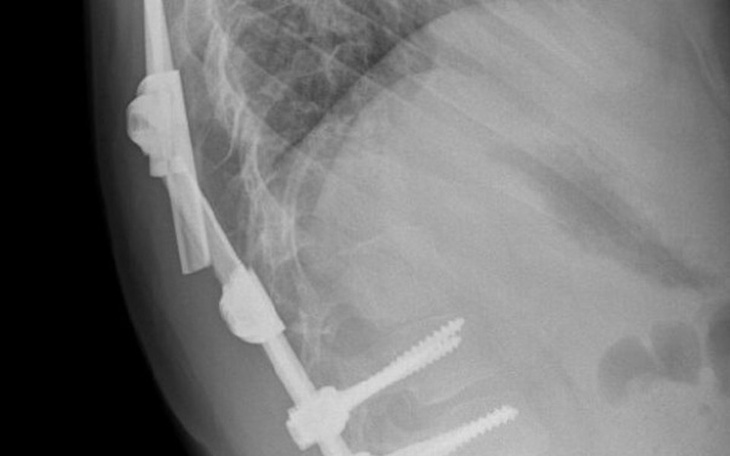

To sa plecy mojego synka pomozcie w zbiorce na gorset

Witajcie jestem mama 3 wspaniałych dziecj.Syn i 2 coreczki syn urodzil sie ze stopa konska szptawa i srodzaona skolioze kregoslupa